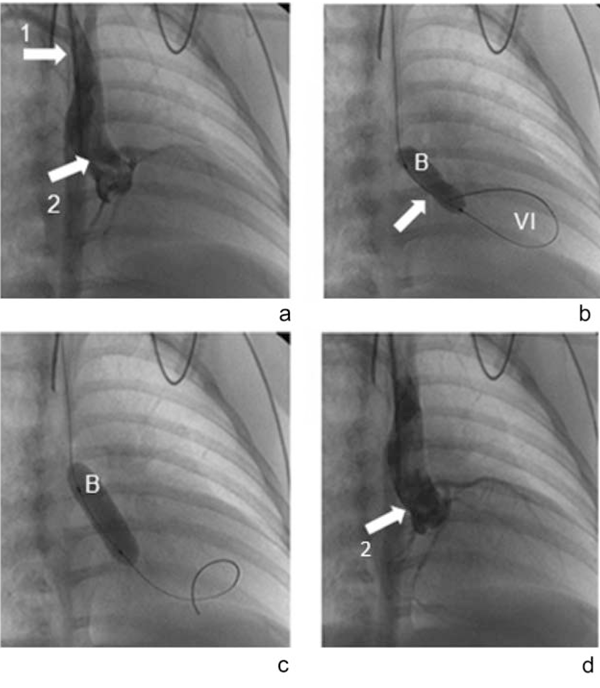

Caso 2: recién nacido de 17 días. Peso al nacer 3.920 g, procedente de Montevideo. Producto de segunda gestación (un aborto espontáneo), embarazo controlado que cursa sin patología. Parto vaginal, circular ajustada de cordón, sexo masculino, edad gestacional clínica 39 semanas. Apgar 8-9. Al segundo día de vida se ausculta soplo sistólico 4/6 y click sistólico en ápex, con pulsos presentes. Se realiza ecocardiograma con Doppler que informa ductus arteriosos permeable de 2 mm con shunt de izquierda a derecha. Válvula aórtica estenótica con gradiente de 75 mmHg. Ventrículo izquierdo hipertrófico. Se realiza de elección valvuloplastia aórtica percutánea (Figura 2). Buena evolución.

Figura 2 a. Aortografía en proyección oblicua anterior derecha. El acceso es por vía de arteria carótida derecha (flecha 1). Se aprecia la válvula aórtica estenótica con un fino pasaje sistólico (flecha 2). b. En proyección oblicua anterior derecha se aprecia la guía ubicada en el ventrículo izquierdo (VI) y el balón (B) insuflado a nivel del anillo valvular aórtico, mostrando en b) la incisura dejada por la estenosis (flecha), que desaparece en c). c. Aortografía en proyección oblicua anterior derecha posvalvuloplastia, observándose mejor apertura sistólica de la válvula (flecha 2).